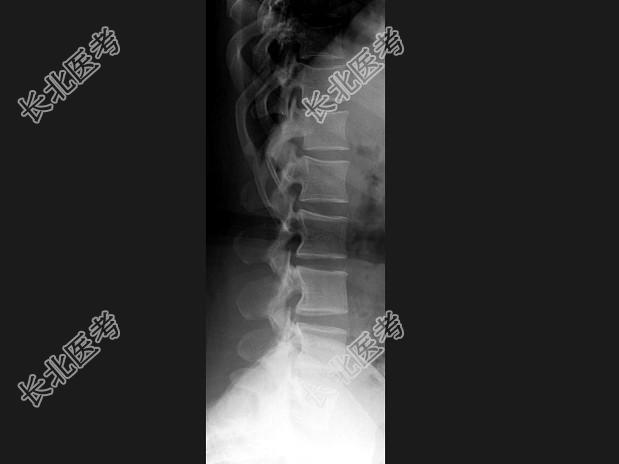

- 单项选择题女,41岁, 身材矮小,背痛, 结合图像,最可能的诊断是 ( )

C、软骨发育不全